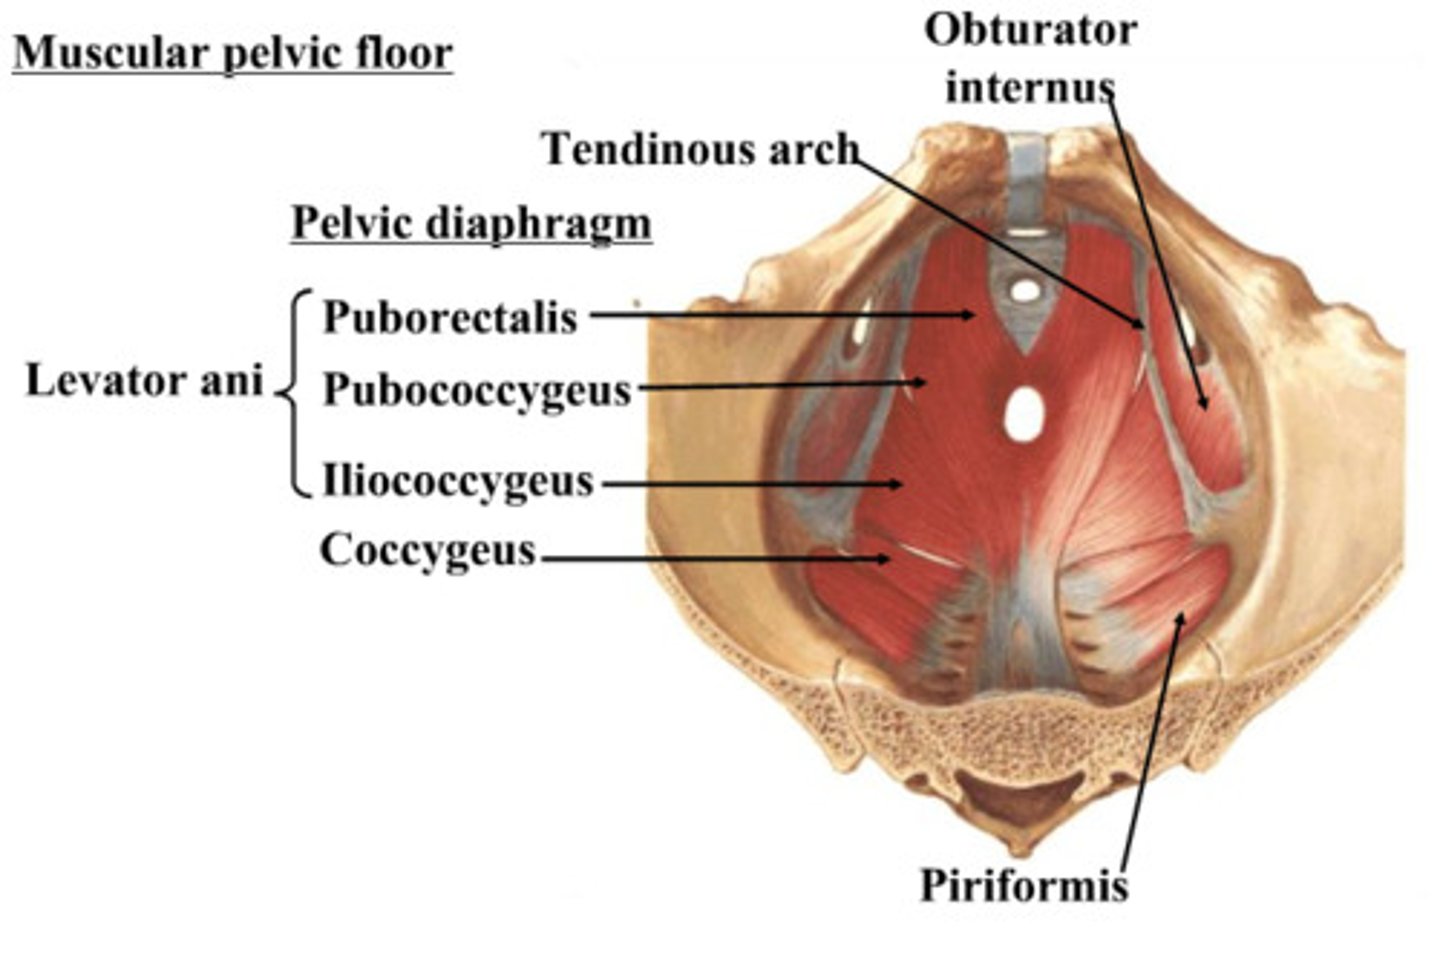

Obturator internus muscles line the ___ walls of the true pelvis

lateral

Piriformis muscles are in the ___ region of the true pelvis behind the ___

posterior; uterus

What muscle is often mistaken for ovaries?

piriformis

What are the 3 levator ani muscles?

pubococcygeus

iliococcygeus

puborectalis